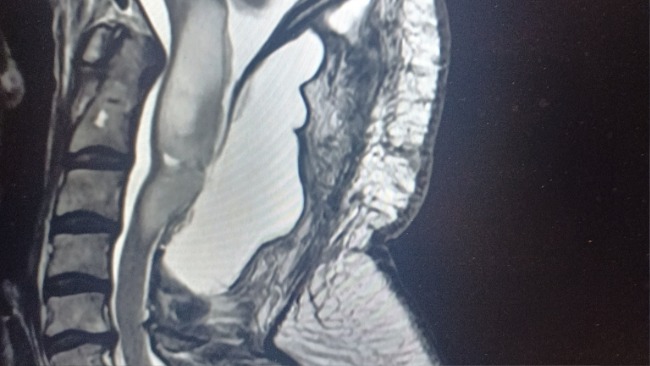

Leczenie trwa, ma leczenie łączone tj. radioterapia plus chemioterapia temozolomidem.